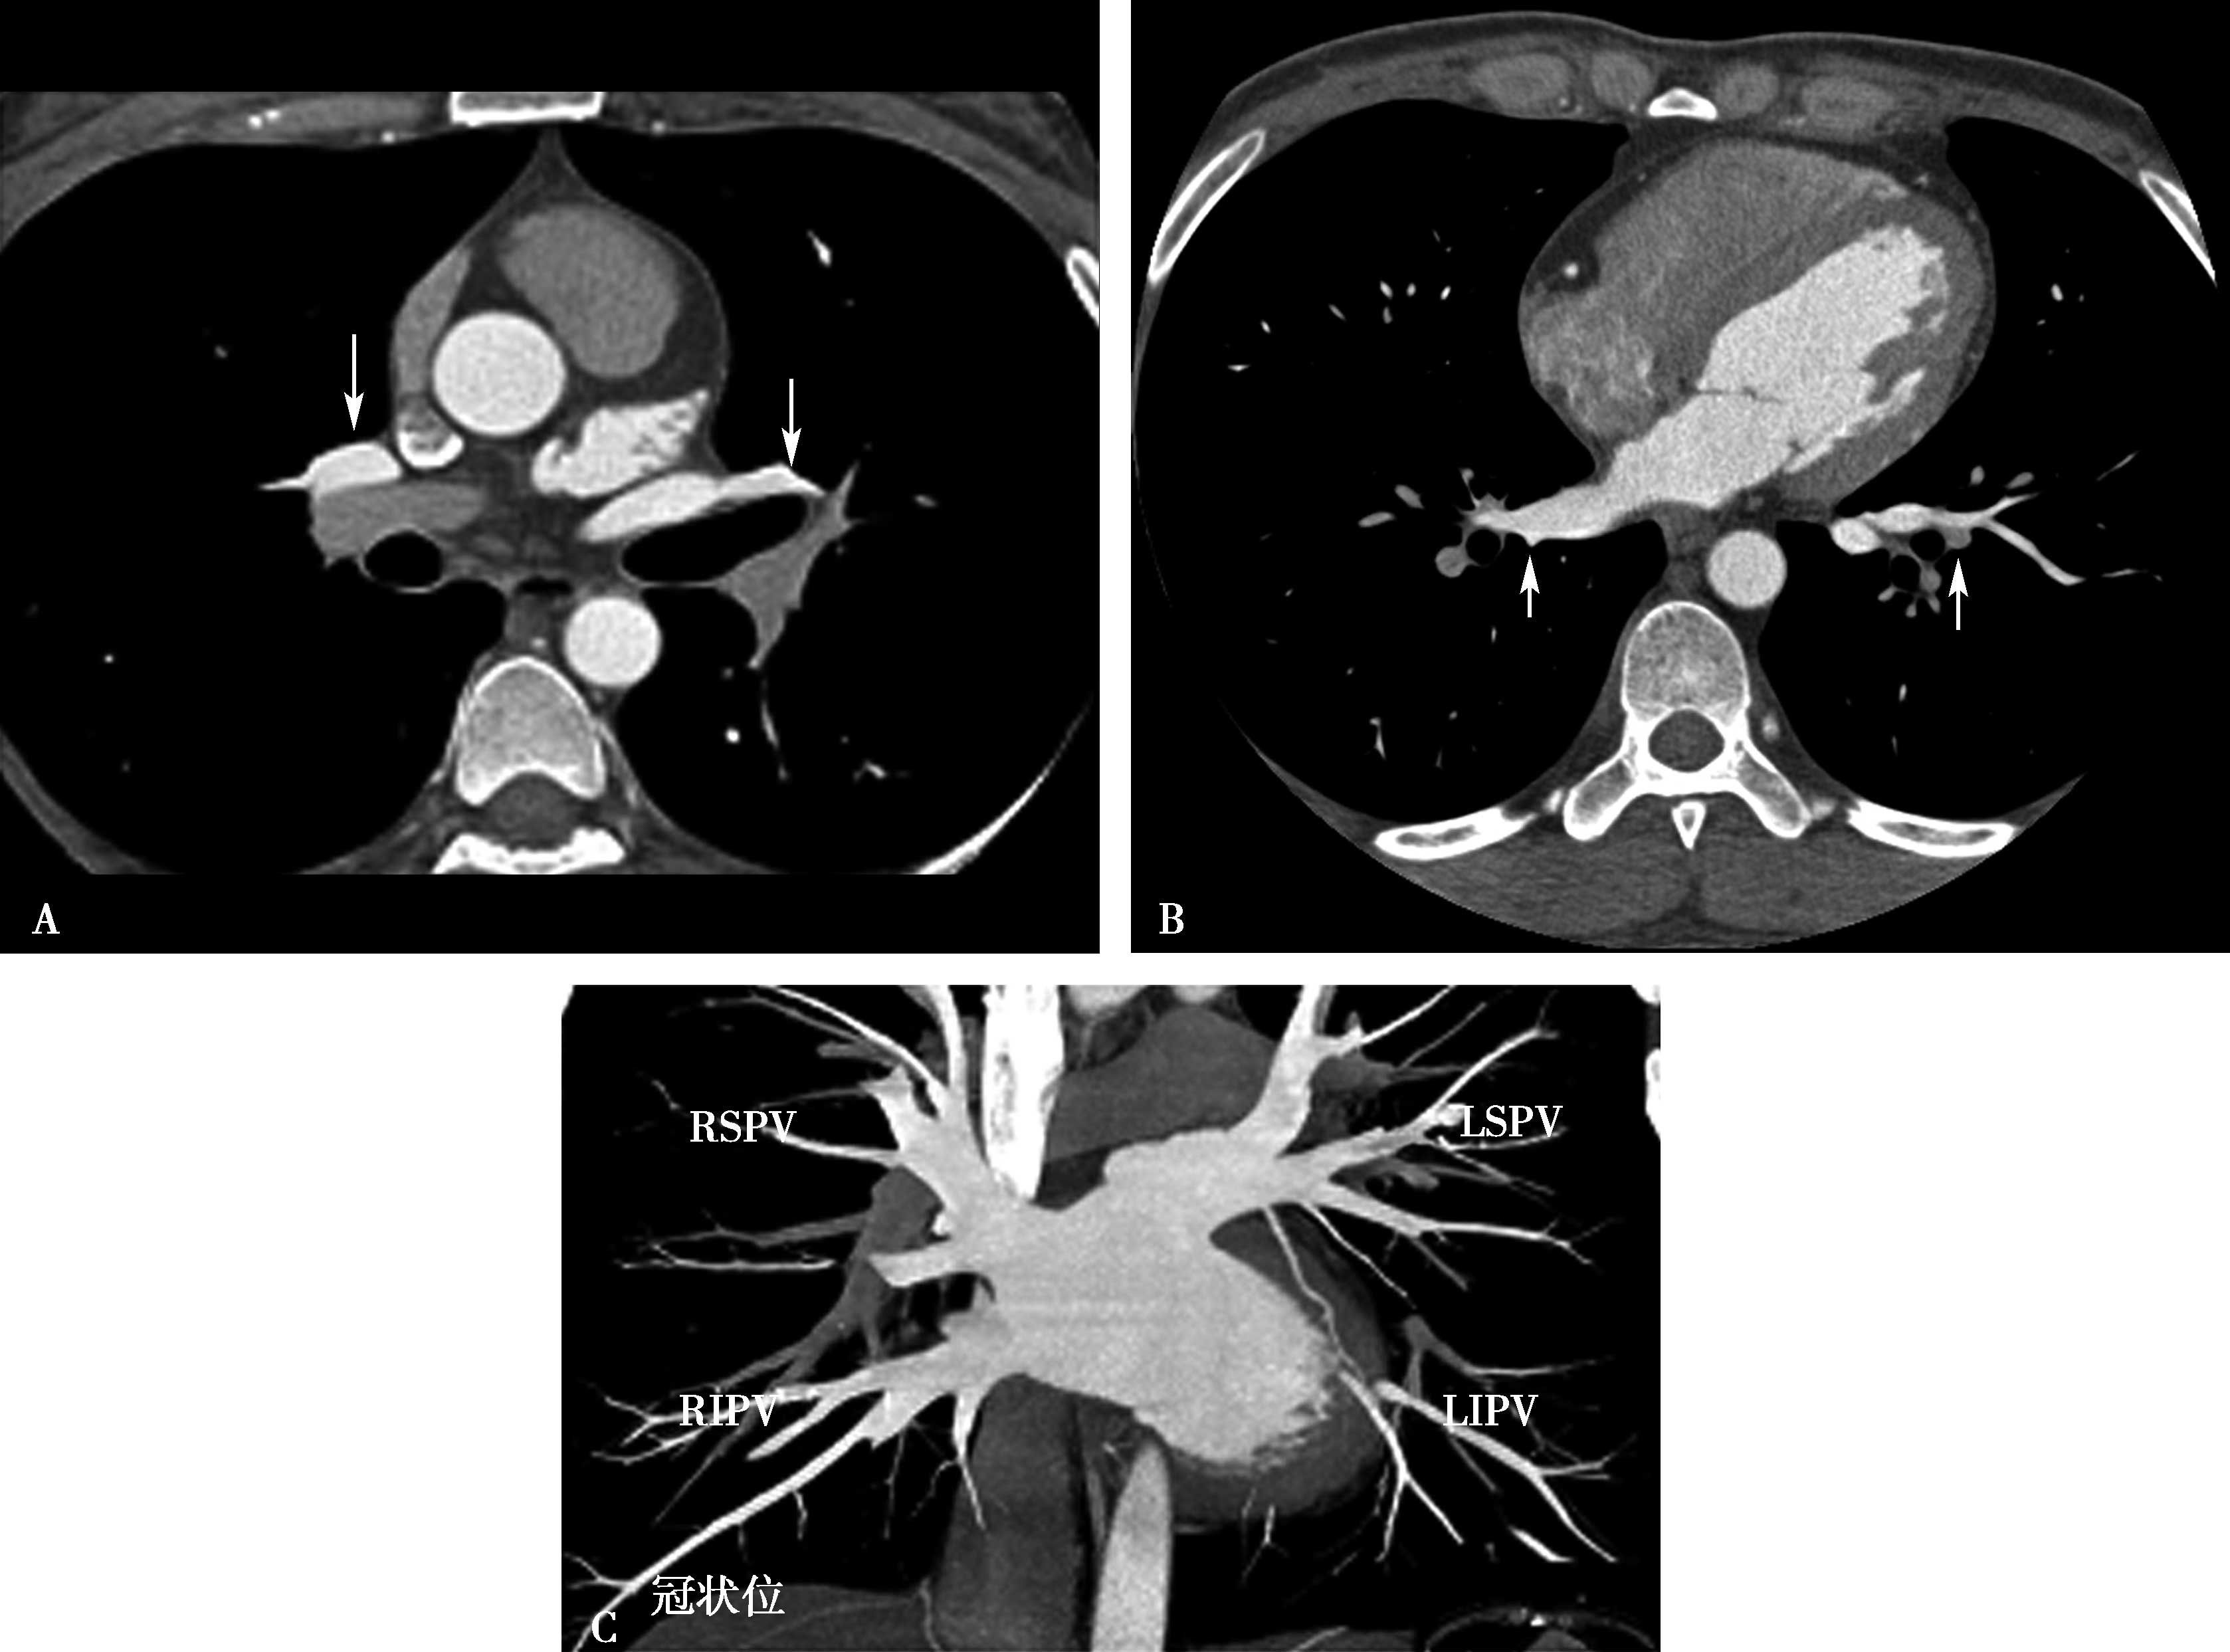

图8-1-11 肺静脉CTA检查

A.上肺静脉(↑);B.下肺静脉(↑);C.肺静脉最大密度投影。LSPV:左上肺静脉;LIPV:左下肺静脉;RSPV:右上肺静脉;RIPV:右下肺静脉